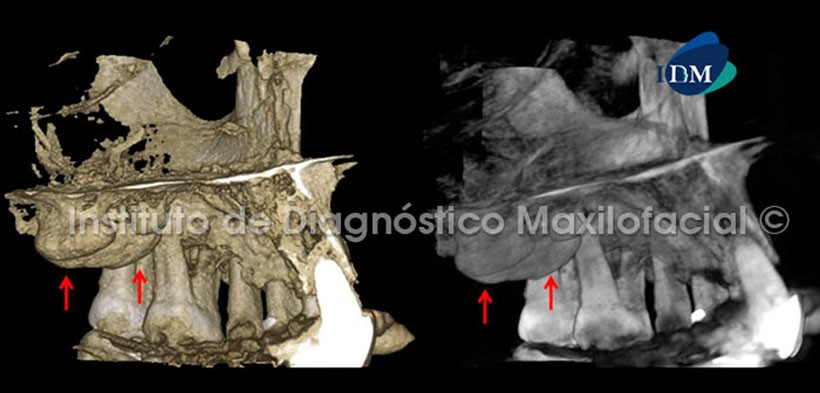

La tomografía computarizada de haz cónico en vistas coronales nos muestra una imagen hiperdensa de forma irregular cuya base se origina en el paladar y que posee características óseas. Signos tomográficos compatibles con Torus Palatino. Se evidencia también zonas de exostosis a nivel de las tablas óseas vestibular y palatina (Fig. 1).

Así mismo, el software Romexis nos brinda diferentes opciones de reconstrucción 3D, como por ejemplo la opción radiográfico matizado que nos muestra preponderantemente las estructuras con alto contenido mineral como el tejido óseo. También tenemos la opción radiográfico que nos ilustra la zona de estudio en escala de grises, la cual complementa de manera ideal la opción anteriormente descrita (Fig. 4, 5 y 6).